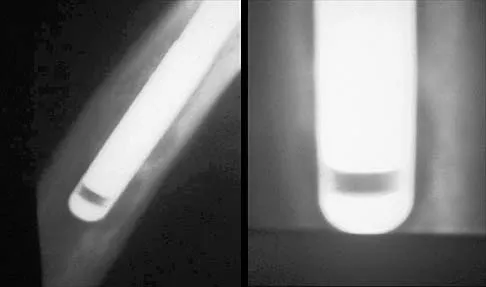

A 21-year-old man who underwent repair of a distal biceps tendon rupture using a two-incision approach 4 months ago now reports difficulty gaining rotation of his forearm. Figures 49a and 49b show the AP and lateral radiographs. What is the most likely cause of his problem?

Explanation